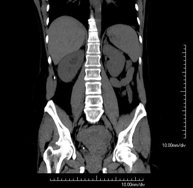

Prova diagnòstica que consisteix en obtenir imatges bi i tridimensionals de l'abdomen d'alta definició anatòmica (estructures òssies, estructures vasculars, fetge, pàncrees, vesícula biliar, ronyons, glàndules suprarenals, melsa, intestí prim i gros, bufeta, úter i ovaris, pròstata i vesícules seminals, urèters, etc.) mitjançant l'ús d'un equip de TC (Tomografia Computeritzada). La majoria d'estudis requereixen l'ús de contrast iodat. - TC Fetge